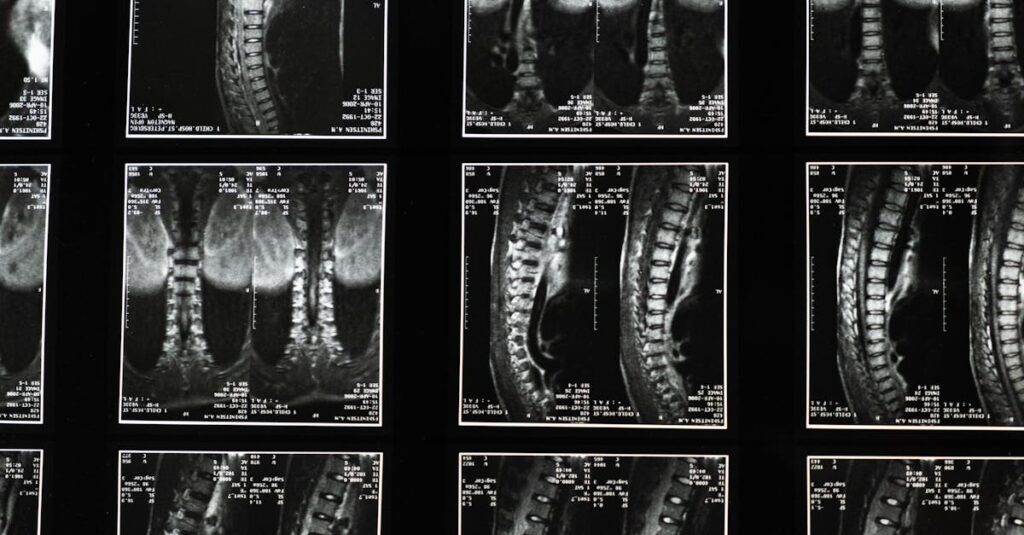

La sciatalgie désigne une douleur qui suit le trajet du nerf sciatique, allant de la colonne vertébrale jusqu’à la jambe. Les symptômes incluent une douleur intense, des sensations de brûlure, des picotements ou des engourdissements. Ces douleurs peuvent résulter de divers facteurs, souvent liés à des problèmes de disques ou de vertèbres.